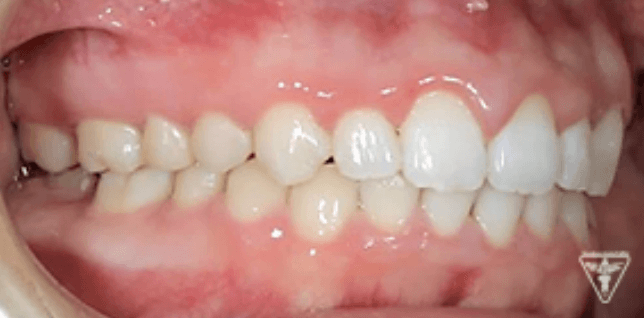

治療後

治療前後の比較